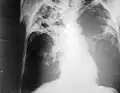

Badanie RTG płuc

Objawy gruźlicy pierwotnej są często mało charakterystyczne, podobne do objawów grypowych. Bardziej zaawansowana postać gruźlicy daje zmiany w płucach w postaci nacieków gruźliczych, widocznych na zdjęciach radiologicznych.

Nacieki gruźlicze w prawym płucu oraz środkowym polu płuca lewego, rozpady (jamy) w górnym i środkowym polu płuca prawego, 2004

Bardzo zaawansowane zmiany. Zmiany gruźlicze przede wszystkim w polu górnym i środkowym oraz jama w szczycie prawego płuca, 2004

Zaawansowane zmiany swoiste (gruźlicze) w obu płucach, 2004

Zaawansowane zmiany swoiste w obu płucach, 2004

RTG klatki piersiowej u pacjenta z obustronną gruźlicą płuc